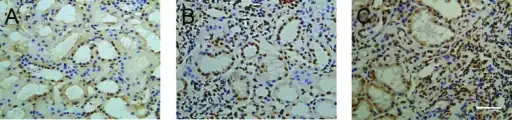

The disease derives its name from deposits of immunoglobulin A (IgA) in a granular pattern in the mesangium (by immunofluorescence), a region of the renal glomerulus. The mesangium by light microscopy may be hypercellular and show increased deposition of extracellular matrix proteins. In terms of the renal manifestation of Henoch–Schönlein purpura, it has been found that although it shares the same histological spectrum as IgA nephropathy, a greater frequency of severe lesions such as glomerular necrosis and crescents were observed. Correspondingly, HSP nephritis has a higher frequency of glomerular staining for fibrin compared with IgAN, but with an otherwise similar immunofluorescence profile.[5]

Morphology

Histologically, IgA nephropathy may show mesangial widening and focal and segmental inflammation. Diffuse mesangial proliferation or crescentic glomerulonephritis may also be present. Immunoflourescence shows mesangial deposition of IgA often with C3 and properdin and smaller amounts of other immunoglobulins (IgG or IgM). Early components of the classical complement pathway (C1q or C4) are usually not seen. Electron microscopy confirms electron-dense deposits in the mesangium that may extend to the subendothelial area of adjacent capillary walls in a small subset of cases, usually those with focal proliferation.